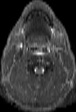

Visible Human male: Sectio transversalis 1225

CT

NMR

Pd T1 T2